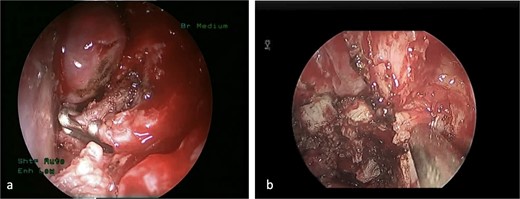

This is a case of a 12-year-old male complaining of nasal obstruction and denying epistaxis, headache, and nasal discharge symptoms. He was found to have bilateral JNA and was successfully treated with embolization of the bilateral distal IMA using polyvinyl alcohol (PVA) particles, followed by surgery. A subtotal resection of the nose, involved sinuses, pterygopalatine fossa, and infratemporal fossa was performed with no postoperative complications (Fig. 8). Six months later, the patient had a recurrence. An in-office endoscopic examination revealed a right-sided mass on the posterolateral wall, necessitating resection. One month prior to surgery, the patient was managed in the emergency department for persistent right-sided epistaxis. It lasted for eight hours and was successfully managed with tranexamic acid. CT imaging showed the recurrent right nasopharyngeal mass with skull extension into the sphenoid sinuses and the right pterygoid plate (Fig. 7a and b). Hence, he underwent embolization of the ECA (Fig. 7c–e). The patient subsequently experienced a decreased level of consciousness, aphasia, and right-sided weakness, with a power of 2/5 in both the lower and upper limbs. MRI showed multiple, extensive punctate foci of cortical and basal ganglia acute infarction complicated by edema, predominantly affecting the left side without a hemorrhagic component. Findings are consistent with showering from the PVA particles (Fig. 7f). A total of 12 months later, the patient was recovered and cleared neurologically to undergo endonasal endoscopic removal for the tumor. The patient was treated surgically at another institution, followed by a course of radiotherapy. Thereafter, he resumed his follow-up in our center, showing no evidence of recurrence after 1 year of follow-up.

(a, b) Contrast-enhanced CT of the paranasal sinuses showing a right nasopharyngeal mass with extension into the sphenoid sinuses and right pterygoid plate. (c) Lateral projection angiogram of the right ICA demonstrating the blood supply to the right nasopharyngeal mass from the inferolateral trunk. (d) Lateral projection angiogram of the right ECA showing extensive vascular supply to the hypervascular mass from multiple branches. (e) Post-embolization right ECA angiogram showing devascularization of the tumor. (f) Transaxial diffusion-weighted imaging of the brain showing extensive foci of restricted diffusion, predominantly involving the left side, consistent with acute stroke.

(a) The sphenopalatine artery is clipped before tumor removal. (b) The vascular tumor is dissected from sphenoplataine and pterygopalatine fossa.